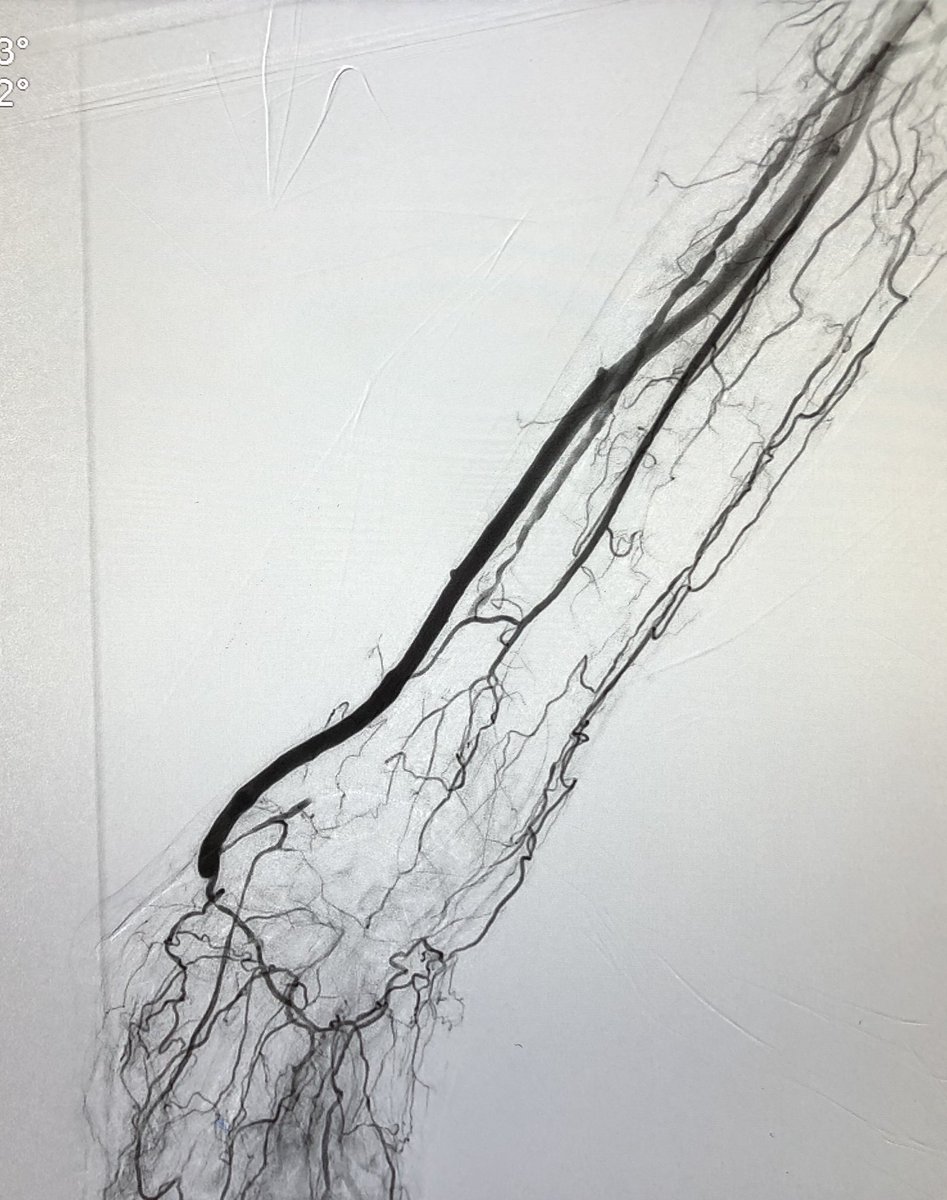

Dan Fremed@DanFremed·

@mattsmeds Still a stubborn up-and-overist- 200 shaft length rx ultraverse balloons have been helpful

Matthew Smeds

Matthew Smeds@mattsmeds·

Anyone doing much pedal arch balloon angioplasty out there? Tips/tricks?